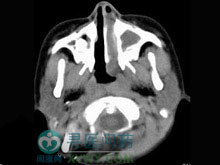

2.影像學檢查

常規的胸部正側位X線片。CT、MRI可見到軟組織腫脹、骨質破壞,有助於了解病變範圍幫助分期。腹部、盆腔超聲。